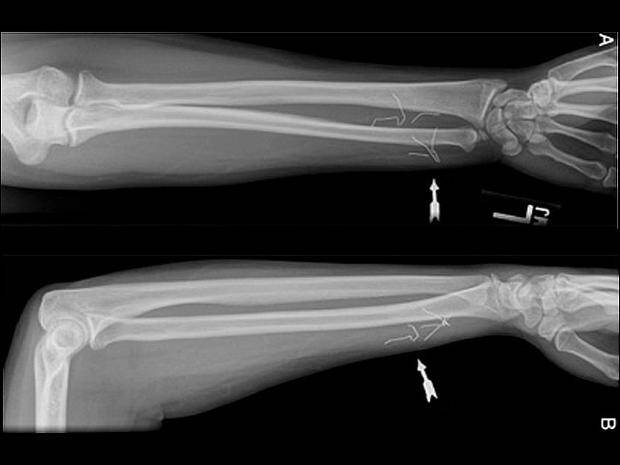

Samookaleczenia są niebezpieczne – oprócz ryzyka wywołania infekcji, umieszczanie w ciele przedmiotów może uszkodzić nerwy lub naczynia krwionośne. – W skrajnych przypadkach oprócz krwawienia (w tym wewnętrznego) może wystąpić nawet udar – powiedział Shiels.

– Jeśli dasz niektórym z tych dzieciaków magazyn do poczytania, to odzyskasz go z brakującymi zszywkami – mówi Shils. – Daj im ołówek, a wyciągną grafit i wsadzą do pod skórę.